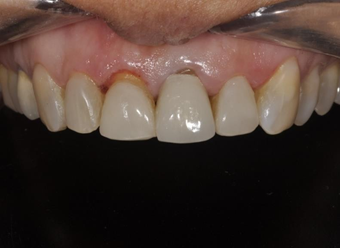

Patient I. A., female, 47 years old, attended the dental office with the chief complaint of dissatisfaction with her anterior teeth and smile. On clinical examination a ceramic veneer was found on tooth 11 with altered color, irregular shape and contour, and on tooth 21 an all-ceramic crown with altered color was found. Both restorations had different colors and volumes, as well as the gingival apex on both teeth was discrepant (Figures 1-3).

Figure 2 Initial photograph with the contrasting black background.